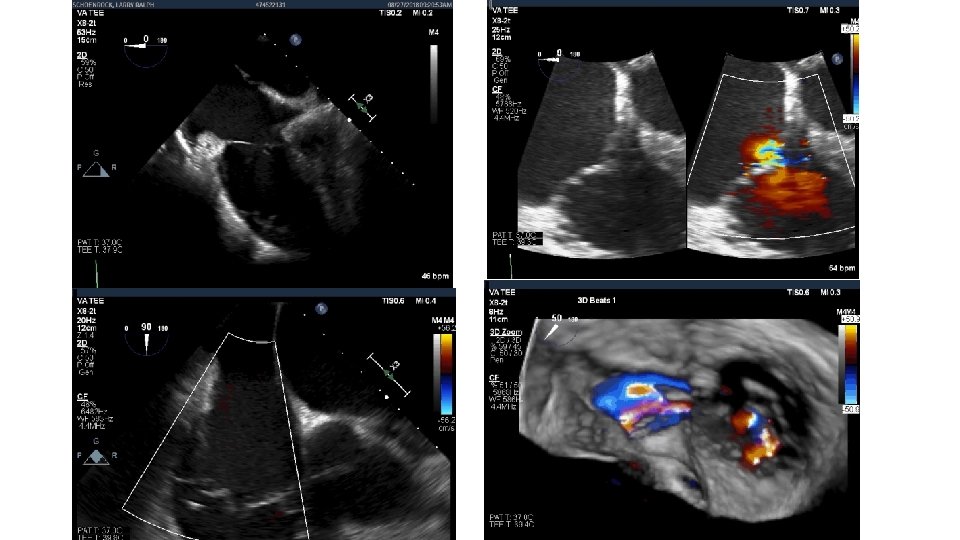

80 yo male with mild dementia referred for evaluation of Progressive dyspnea >1 year Exam: venous distention, TR murmur, no RV lift Creat 2. 2 Transthoracic Echo: Isolated severe TR. IVC 3. 3 cm. RA is dilated RV normal function. Dilated annulus (4. 2 cm)-presumed mechanism of TR. TEE, right heart catheterization RAP 16, and coronary angiography: non obstr CAD What do you do next? Medical management, Refer to CV surgery , other options

Tricuspid Valve (TV) Imaging • TV imaging is challenging • Three TV leaflets (anterior, septal and posterior) are thin and membranous Huitin et al. Archives of Cardiovascular Diseases Volume 109, Issue 1, January 2016, Pages 67 -80

• TV assessment • severity of TR • Mechanism of • mode of leaflet coaptation, • degree of tricuspid annulus enlargement and tenting • TAPSE • 3 D-TEE • Cardiac CT • cardiac MRI